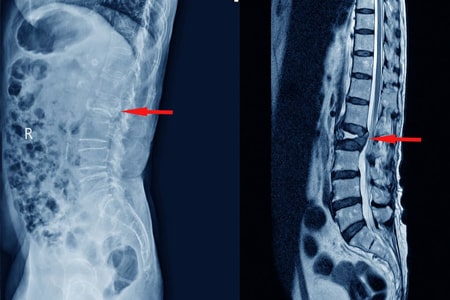

Los AINE y la teriparatida pueden ser las opciones de tratamiento preferidas para el tratamiento del dolor agudo en las fracturas vertebrales por compresión osteoporóticas. Aunque la calcitonina también demostró ser beneficiosa, su perfil de seguridad y los posibles efectos adversos restringen su aplicación generalizada. La evidencia limitada sobre los aparatos ortopédicos y los analgésicos subraya la necesidad urgente de investigaciones futuras. JAMA Netw Open. 3 de septiembre de 2024